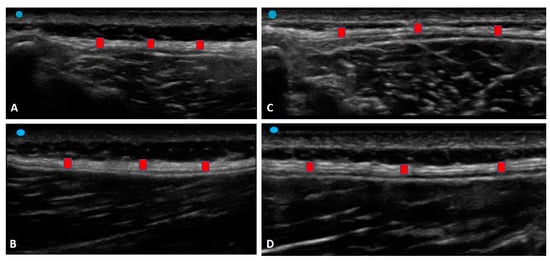

Myofascial pathways of force have been observed at various levels including between adjacent fibers [35]. The use of advanced magnetization transfer contrast imaging (MRI) has demonstrated the effect of aging but also the effect of disuse on the remodelling of the extracellular matrix by force transmission in the human musculoskeletal system [36]. Indeed, in chronic non-specific LBP patients, some authors have suggested micro-injuries of paraspinal connective tissue and the TLF as possible causes of LBP [37]. Adhesions between TLF layers and epimysium of the erector spinae and multifidus muscles and densification of the TLF are considered determinants of LBP [38]. All of this alters and limits daily movement determining the flaccidity of lumbar segments and altered pattern motion [12]. That being said, the alteration in the muscle activation patterns in chronic non-specific LBP patients modifies the proprioception of these subjects in a cascade (Figure 5).

Figure 5.

Ultrasound images of the TLF thickness: (A) Group 1: transverse axis; (B) Group 1: non-tensional force on the TLF; (C) Group 2: TLF profile in the transverse axis; (D) Group 2: TLF profile in the transverse axis. Red square: TLF.

Furthermore, the correlation between VAS and US TLF thickness in the right transverse axis for group 1 (r = 0.2920; p = 0.049) could be explained by the fact that after the TLF becomes densified and sensitized, those free endings will be more and more stimulated when the TLF is strained by the contraction of the muscle. For this reason, a vicious circle of a “frozen back” leads to fascial remodelling that blocks the stretch of free nerve endings to reduce pain, maintaining homogeneous and greater thickness.